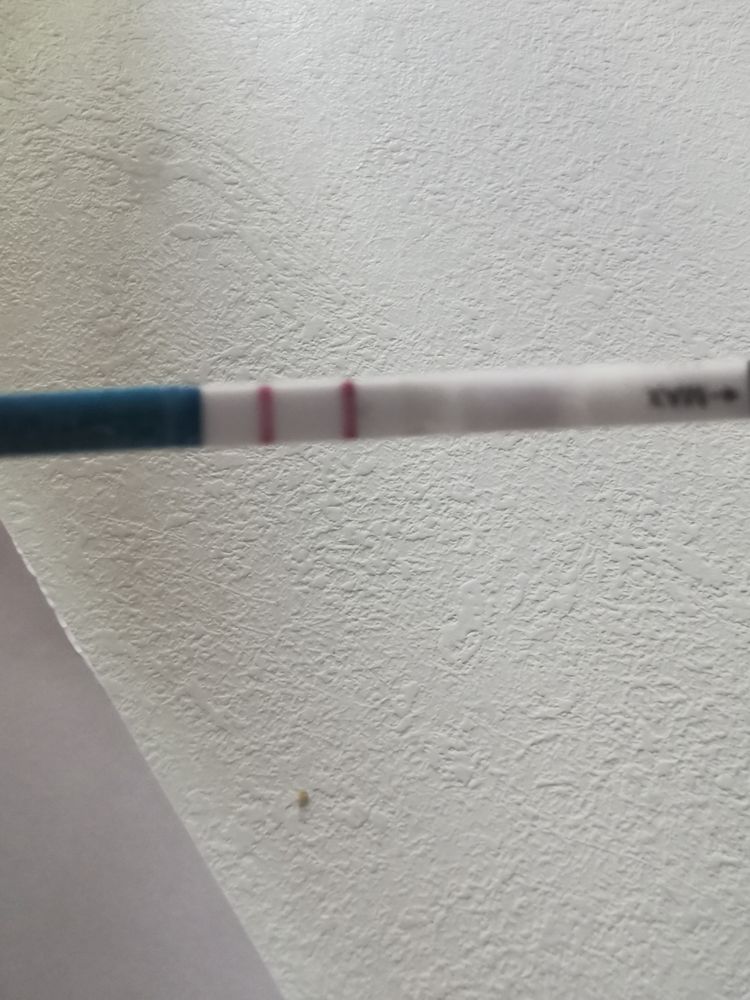

🌿15 тестов на беременность 🤦♀️🙆♀️